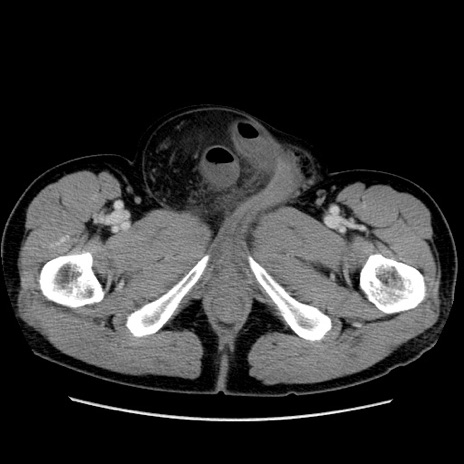

症例34(横断像)

【症例】60歳代 男性

【主訴】右鼠径部膨隆

【現病歴】1年程前より右鼠径部膨隆あり。自己にて還納可能だったため放置していた。3時間前より右鼠径部の脱出を認め、還納困難となり受診。

【既往歴】高血圧

【身体所見】右鼠径部に小児頭大の膨隆あり。弾性硬であり、用手還納は困難。左鼠径部にも膨隆を認める。脱出はなし。

【データ】WBC 15500、CRP 測定なし